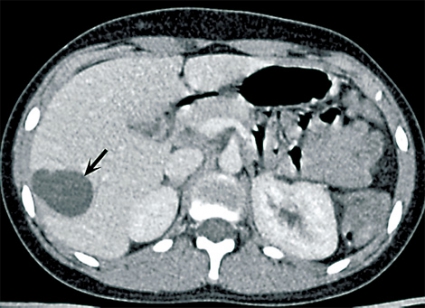

Fall 2. En 34-årig man från Tunisien sökte vård för buksmärta och hög feber. Patienten var ikterisk och visade tecken till gallstas. Antibiotikabehandling inleddes då den kliniska bilden talade för kolangit. Utredning med ultraljud och DT påvisade två cystiska förändringar i levern (5 respektive 6 cm stora), båda såg ut som ekinokockcystor. Blodprov visade stegrat CRP och eosinofili. Serologisk diagnostik bekräftade diagnosen. Gallvägarna avlastades med stentning via endoskopisk retrograd kolangiopankreatografi (ERCP) på grund av en intrahepatisk striktur (Figur 2). Behandlingen förbättrade initialt kolangiten, men patienten fick flera recidiv.

Radiologisk utredning av ekinokockcystor har flera målsättningar. Den ska bidra till diagnostiken och till en anatomisk kartläggning av utbredning och eventuella komplikationer, bedöma cystans viabilitet och underlätta preoperativ planering. Den radiologiska diagnostiken av ekinokockcystor i levern har centrerats runt ultraljud men har på senare tid ofta ersatts med DT och MR. Radiologiska fynd som talar för ekinokockcysta utgörs framför allt av cystvägg med dubbelkontur, multivesikulärt utseende och väggförkalkningar (talar för inaktiv cysta). Viktigt att komma ihåg är att kalcifiering av väggen förekommer inte bara vid inaktiva (CE4 och CE5) cystor utan även i upp till 50 procent vid alla stadier [7]. WHO-klassifikationen av ekinokockcystor grundas på ultraljudsundersökning men kan överföras till antingen DT eller MR [2, 3]. Cystans relation till gallvägar, kärl och extrahepatisk vävnad bedöms enklast med DT eller MR. Om fistulering till gallvägar misstänks kan MR med kolangiopankreatikografisekvenser och i vissa fall endoskopisk retrograd kolangiopankreatikografi (ERCP) bidra till noggrann anatomisk kartläggning inför planerad resektion [8].